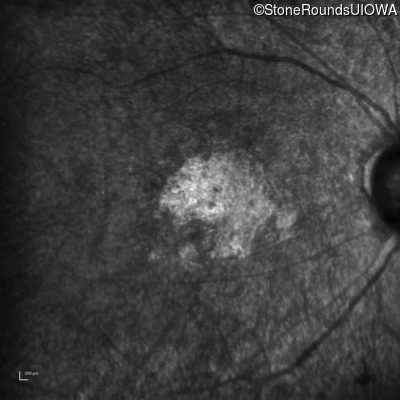

The clinical features supporting the diagnosis of Bardet Biedl syndrome in this patient include: bone-spicule-like pigmentation, narrowed arterioles and macular atrophy on ophthalmoscopy; photoreceptor loss on OCT; ulnar polydactyly, obesity, abnormal cognition, hypertension; and, normally sighted parents.